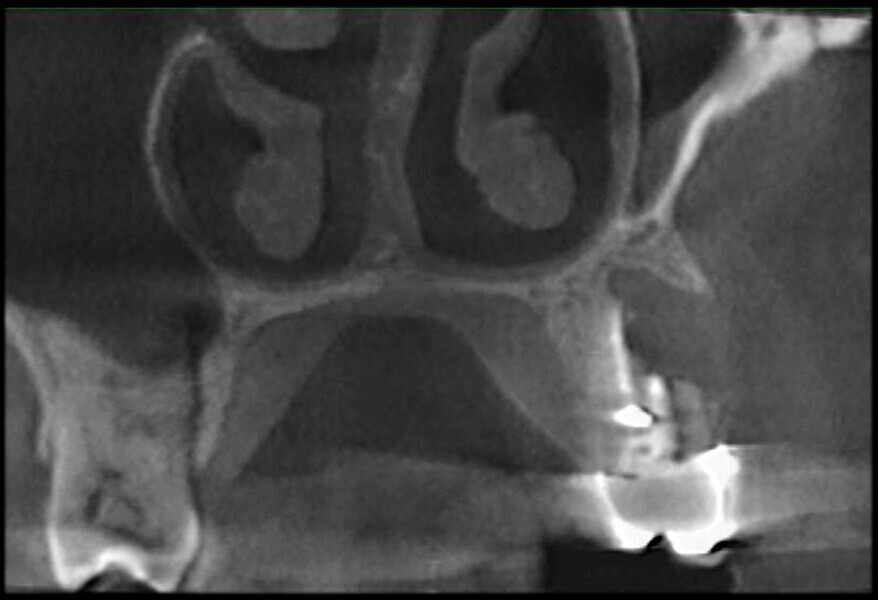

Use of 3D technology in the diagnosis and treatment of endodontic disease